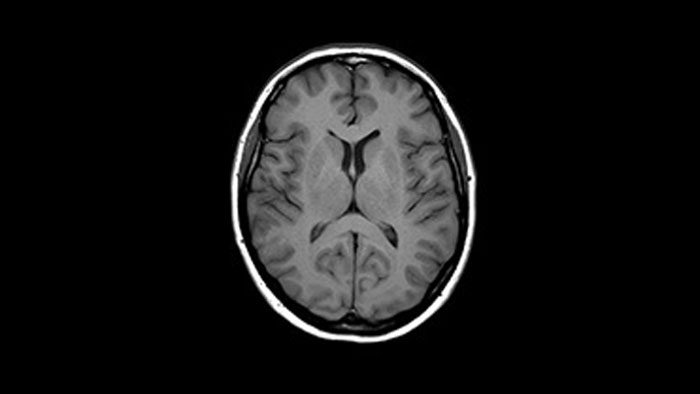

A revolutionary breakthrough in diagnostic quality – and speed

3.0T imaging at your fingertips

Enhanced diagnostic confidence in neuro oncology